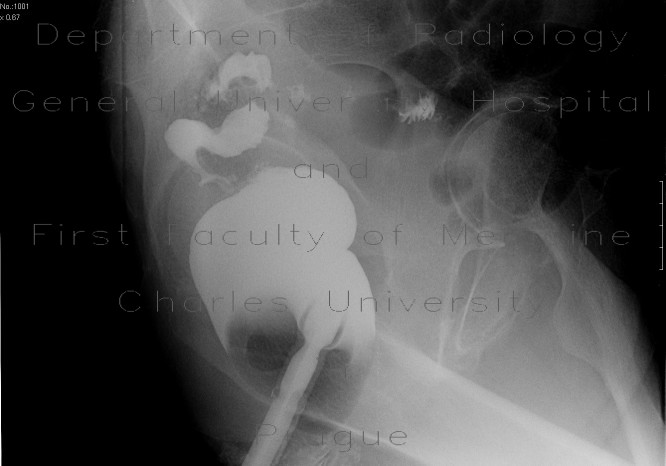

Descending colon stenosis As A Complication Of ... - Termedia

Przegląd Gastroenterologiczny 2009; 4 (1) Descending colon stenosis as a complication of acute pancreatitis Zwê¿enie zstêpnicy jako powik³anie ostrego zapalenia trzustki ... Retrieve Here